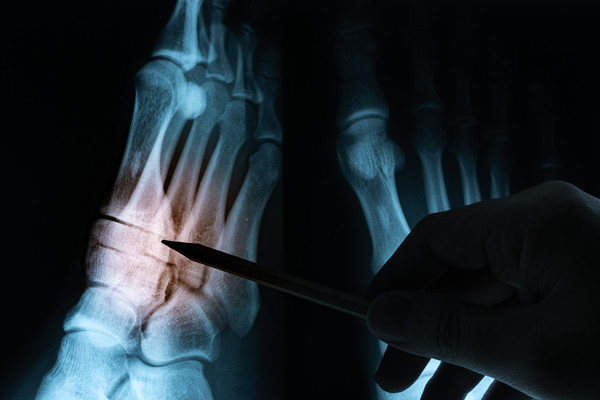

早前有一患者因为出现相关症状去医院就医检查,结果诊断出是骨结核,通过影像检查来看,病情发展的已经非常严重了,医院是建议手术治疗,但由于骨结核发病部位比较特殊,医生考虑风险较大,于是建议先保守治疗,所以在常规抗结核治疗基础上联合中医一起治疗。

中医治疗主要是选择中药内外兼治,内服为其配制的补肾壮骨、温经散寒、化痰散结之丸药,同时在外敷一些膏药,经过一段时间的保守治疗后,再随访检查发现破坏的骨质已经有明显的修复,而且患者症状已经改善了很多。